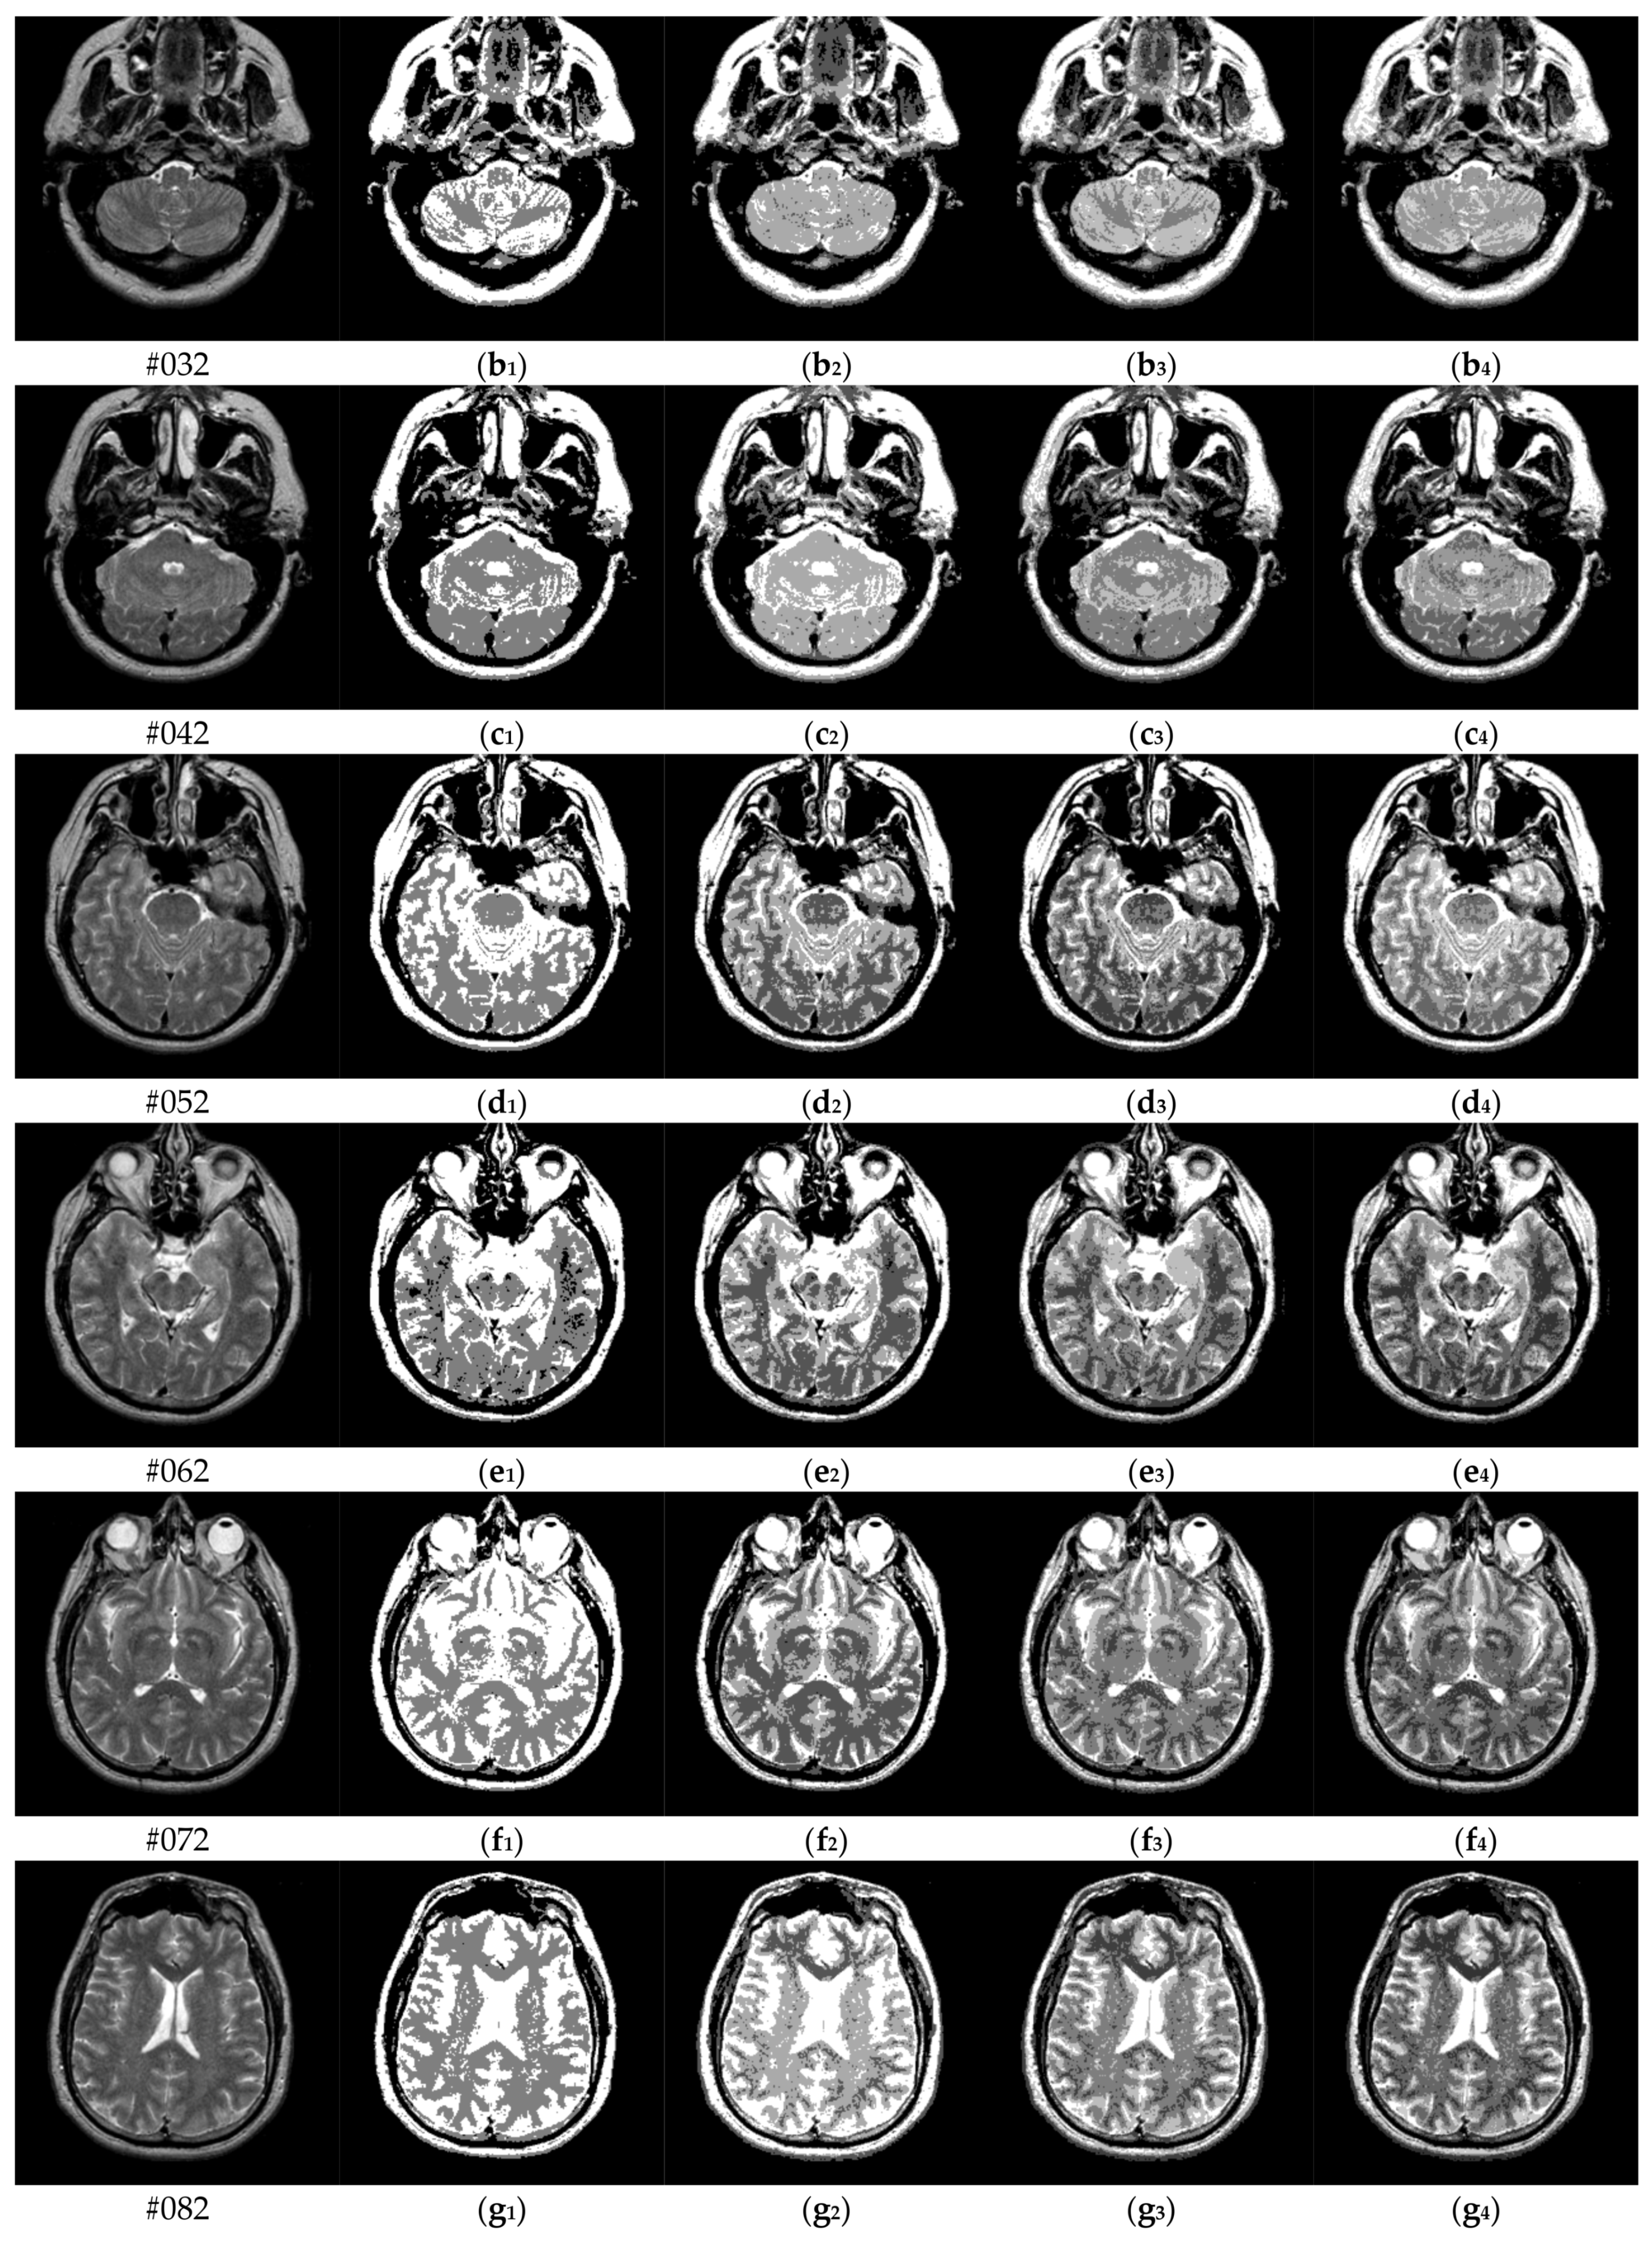

To verify the performance of the proposed algorithm, five representative multi-threshold segmentation algorithms are selected for comparative experiments. The five comparative experimental algorithms are: (1) image threshold segmentation algorithm based on particle swarm optimization (PSO), (2) image threshold segmentation algorithm based on bacterial foraging (BF), (3) image threshold segmentation algorithm based on adaptive bacterial foraging (ABF), (4) image threshold segmentation algorithm based on Nelder-Mead simplex (NMS), (5) image multi-threshold segmentation algorithm based on real coded genetic algorithm (RCGA) [43]. The number of thresholds is set to K = 2, 3, 4, and 5, respectively. Due to the limited space, we only show the segmentation results of the proposed algorithm in this paper. Figure 8 shows the segmentation results of Slice#022~#112 when the threshold K = 2, 3, 4, 5. Intuitively, the proposed algorithm can better segment each region of the experimental image, and the continuity of different regions is well guaranteed. At the same time, the visual effects are satisfactory.

Figure 8.

Segmentation results obtained by the proposed algorithm for brain slices #022~#112; (a1–j1) display the results of 2-thresholding; (a2–j2) display the results of 3-thresholding; and (a3–j3) display the results of 4-thresholding; (a4–j4) display the results of 5-thresholding.

The uniformity measures (U) values of the proposed algorithm and other comparison algorithms with K = 2, 3, 4, 5, respectively, are shown in Table 2. The highest U values are marked in bold. In general, our proposed algorithm achieves the best or better evaluation results on all test images. For #042, #052, #062, #082, #112, the proposed algorithm achieves suboptimal results when K = 5. The difference of the objective evaluation U value is small and acceptable. Overall, our proposed algorithm achieves the best segmentation results in test images, outperforming five different contrasting algorithms.